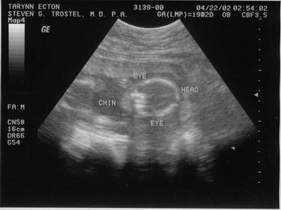

Second Sonogram, taken 04-22-02.

04-22-02 - Looks like I'm a GIRL!